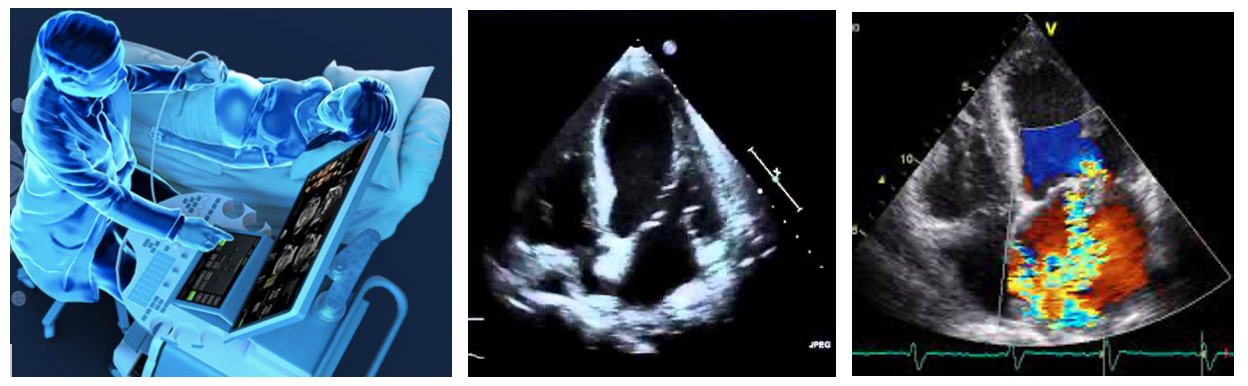

- Echocardiogram is similar to the ultrasound scans done during pregnancy. This test can assess the heart muscle, valves and the pressures in the heart. This determines how well the heart functions.